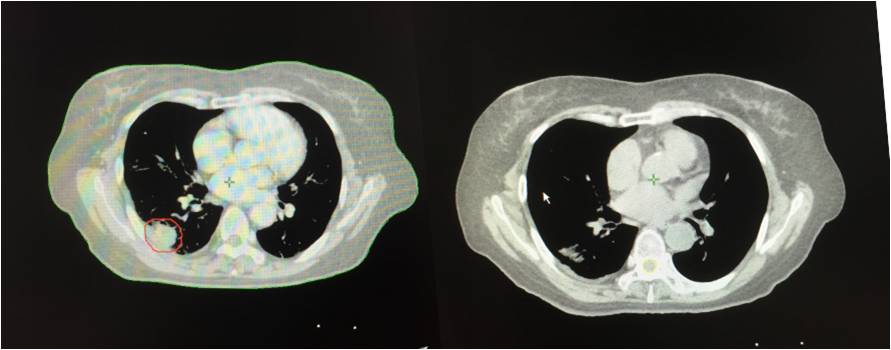

治疗前 治疗后

2013年3月初无明显诱因出现胸闷、气短,活动时加重,伴有间断左侧肩胛区疼痛,无咳嗽、咳痰,无发热、咯血,无盗汗、乏力。2013年4月胸部CT示:右肺占位。4月末在北京大学人民医院行胸部CT增强示:双肺下叶背段恶性病变,考虑肺癌可能性大。5月在*警武**北京总队第二医院行PET/CT检查提示:1.双肺下叶背段斜裂胸膜下高代谢结节,考虑恶性病变,肺癌可能大,双肺多发磨玻璃结节及微小结节,未见明显高代谢,倾向恶性病变;2.右乳外下象限小结节伴代谢,结合临床。

2013年5月入院,肺穿刺病理结果提示:左下肺腺癌。

2013年5月、6月接受四次A45肿瘤治疗治疗四次。2013年10月再次接受全身A45肿瘤治疗1次,右下肺病灶A45肿瘤治疗1次,出院后继续口服易瑞沙靶向治疗。患者肿瘤缩小,几乎消失。患者的状态稳定。